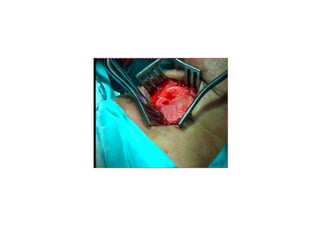

M KROLARENGOSKOP

(Direkt larengoskopi ve

mikroskopi alt nda eksizyon)

BoyceBoyce -- JacksonJackson

(koklama) pozisyonu(koklama) pozisyonu

SES VE KONU7MATERAP S M KROLARENGOSKOP (Direkt larengoskopi ve mikroskopi alt nda eksizyon)

BoyceBoyce -- JacksonJackson (koklama)pozisyonu(koklama) pozisyonu